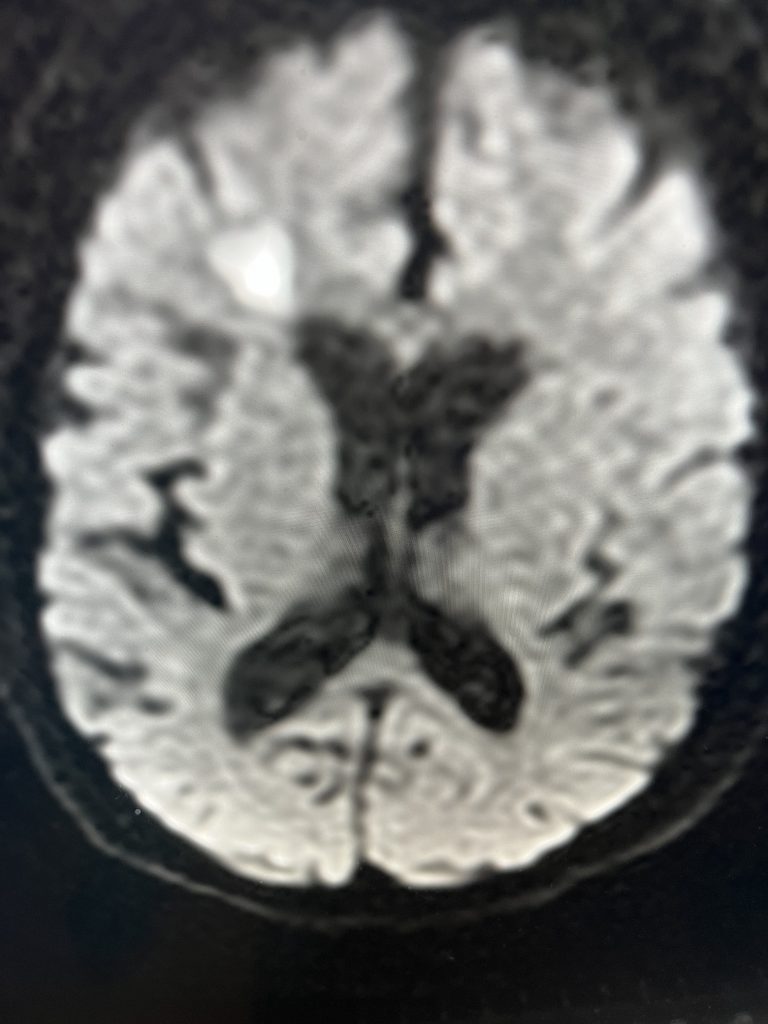

Fig. 2 – Pre-operative imaging shows multiple areas of most likely embolic stroke in the right corona radiata.

MRI imaging using the diffusion-weighted image sequence, which is highly sensitive for acute stroke showed multiple areas of most likely embolic stroke in the right frontal white matter (Figure 1) as well as the right corona radiata (Figure 2).